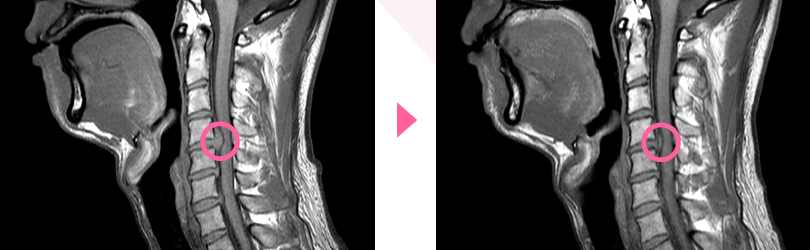

1年前は、股関節の痛みでほぼ歩けない状態になり、

病院では、人工股関節の手術を勧められていました。

KWS®に来られてたった2回目で痛みがなくなり、

今ではこのように歩けるようになりました。

1年経ちましたが痛みは出ておりません。